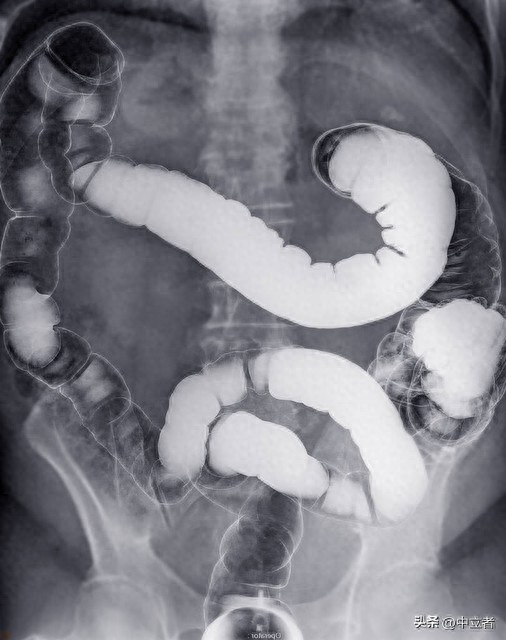

肠癌是一种常见的恶性肿瘤,但其早期症状常常被忽视。然而,大便的异常变化可能是身体发出的健康警示信号之一。通过观察大便的颜色、形状、质地和气味等方面的变化,我们可以更早地察觉到潜在的健康问题,包括可能存在的肠癌。

1. 定期体检与筛查定期体检是预防肠癌的重要手段之一。结肠镜检查是一种常用的筛查方法,可以及早发现肠道异常情况,包括息肉和肿瘤。建议中老年人定期进行结肠镜检查,以提高早期发现肠癌的机会。2. 健康生活方式保持健康的生活方式对预防肠癌至关重要。合理饮食、适量运动、充足睡眠以及减压都可以有助于维护消化系统健康。避免高脂肪、高热量食物的摄入,增加膳食纤维摄入量,有助于降低患肠癌的风险。3. 早期发现与及时治疗如果出现大便异常或其他消化系统问题的症状,应尽早就医。及时发现并治疗肠癌可以提高治愈率和生存率。与医生合作,制定适合自己的治疗方案,积极配合治疗过程,可以帮助尽早战胜疾病。通过观察大便信号并采取预防措施,可以降低患肠癌的风险,保障身体健康。